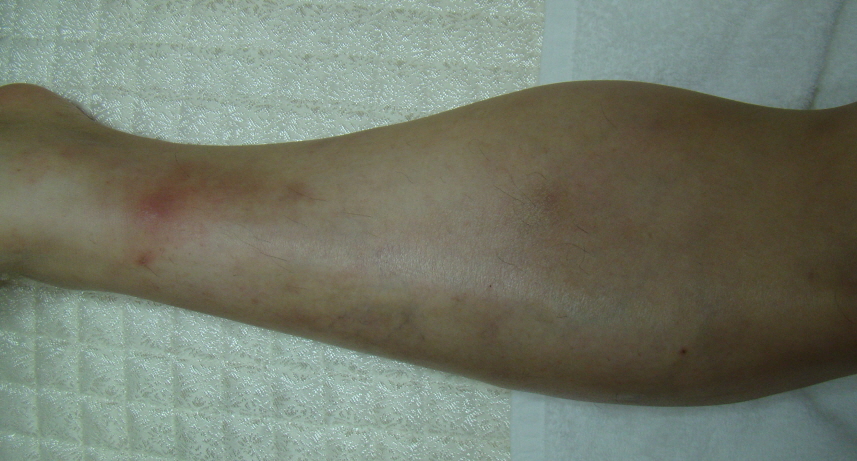

결절홍반과 감별해야할 질환으로는 경결홍반이라는 질환이 있습니다. 30대 이후의 여성에게 많이 발생하는 질환이며, 압통을 동반한 결절이 하지에 대칭적으로 발생합니다.

<경결홍반, 결절성혈관염>

경우에 따라서는 궤양이나 색소침착이 동반될 수 있습니다. 몽우리가 만져지는 결절과 만지면 아픈 것이 결절홍반과 비슷하지만 염증으로 인한 열감이나 전신증상은 결절홍반보다 미비합니다.